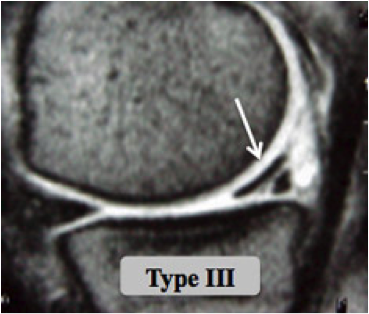

Des examens plus spécifiques comme l'IRM et l'arthroscanner sont demandés si les radiographies sont normales; ils vont permettre de visualiser les structures ménisco-ligamentaires et cartilagineuses de l'articulation.

Les lésions horizontales sont le résultat des forces en glissement. La notion de traumatisme initial peut manquer.

Les lésions intracorporéales sont secondaires aux forces en cisaillement, siégeant souvent dans le segment postérieur du ménisque interne.